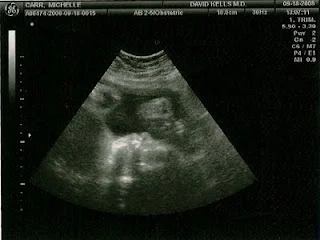

We started 2 a week doctor's appointments. Last week we had an ultrasound and they said Jackson weighs a whopping 4 1/2 pounds (at 32 weeks)! Yikes. Nicholas was only 2 1/2 pounds when he was born at 29 weeks so no wonder I'm starting to feel some aches & pains. I never got this far last time. It's actually exciting to go twice a week. They do an ultrasound once a week and a non-stress test both visits. We get to see the baby and then get to hear his heart beating and movements for about 20 minutes. It's re-assuring, and even better this time no sign of high blood pressure. The doctor says everything looks the way it should. My c-section is scheduled for November 12. So I fully intend for this little guy to stay put in my tummy until then.

Here are some ultrasound pictures from last week and today:

Last week:

And Today:

It's fun seeing our little guy grow.